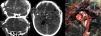

Pero además consideramos que puede extenderse a otros supuestos en los que la situación de descompresión no es secundaria sino primaria, como ocurre en los traumatismos craneoencefálicos con estallido y/o las lesiones por arma de fuego con munición de grueso calibre (fig. 1), excepcionales en nuestra práctica habitual. Estos pacientes presentan aun menos dudas sobre la irreversibilidad del proceso de daño encefálico.